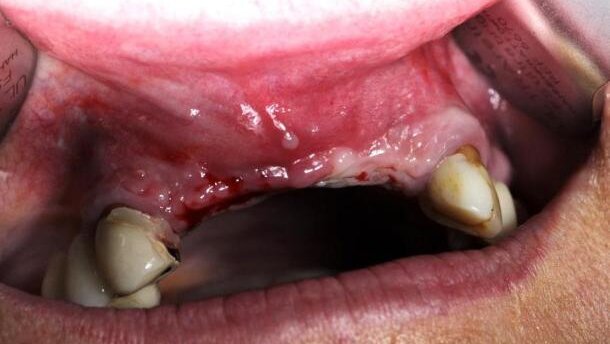

Celem prezentowanej pracy jest porównanie 2 przypadków leczenia implantoprotetycznego bezzębia przedniego odcinka szczęki (4 zęby sieczne). W pierwszym przypadku zastosowano odroczoną instalację implantów przy zanikłej błonie śluzowej i braku brodawek międzyzębowych, u drugiego pacjenta wykonano natychmiastową instalację implantów w zębodoły poekstrakcyjne wraz z augmentacją tkanki kostnej i mobilizacją błony śluzowej zgodnie z zasadą bez napięcia tkanek.

40-letnia pacjentka zgłosiła się w celu leczenia implantoprotetycznego brakujących 4 górnych siekaczy. Zęby utraciła przedwcześnie, co skutkowało zanikiem brodawek międzyzębowych między siekaczami bocznymi i przyśrodkowymi oraz inwolucją brodawki przysiecznej i ścieczeniem błony śluzowej w odcinku bezzębnym wraz z obniżeniem wyrostka zębodołowego. Warunki kostne pozwoliły na instalację 4 implantów o wymiarach 3.25 x 11.5 Biomet 3i NanoTite Tapered Certain. Na czas gojenia pacjentkę zaopatrzono w częściową protezę górną podścieloną na miękko materiałem Ufi Gel P. Rozległość braku zębowego uniemożliwiała wykonanie tymczasowej odbudowy stałej przy pomocy mostu adhezyjnego. Po 6 miesiącach implanty odsłonięto i zmierzono stopień integracji urządzeniem Ostell. Pomiary wyniosły odpowiednio:

U 50-letniej pacjentki wykonano ekstrakcję zębów 12, 11, 23, będących filarami dla mostu porcelanowego z powodu 2 stopnia ruchomości zębów wg skali. Natychmiastowo zainstalowano 4 implanty Biomet 3i Osseotite Tapered Certain o wymiarach 4 x 11.5 (pozycja 12), 4 x 10 (pozycja 11), 4 x 11,5 (pozycja 21/22) i 4 x 10 (pozycja 23). Wykonano jednoczesną augmentację kości, stosując Bio Oss/Bio guide. Ranę szczelnie zszyto.

Ekstrakcja 4 siekaczy szczęki powoduje znaczny zanik tkanki kostnej, nasilający się z czasem z powodu braku funkcji, prowadząc do łukowatego kształtu zanikłego brzegu wyrostka. Nasila to niemal całkowity zanik brodawek międzyzębowych oraz ścieńczenie błony śluzowej w bezzębnym odcinku.

Natychmiastowa poekstrakcyjna instalacja implantów w strefach zębododołowych z jednej strony przeciwdziała resorpcji tkanki kostnej, z drugiej, podtrzymując brodawki międzyzębowe, ogranicza ich zanik. Wydaje się, iż o ile wskaźnik przetrwania implantów (implant survival rate) w natychmiastowej poekstrakcyjnej instalacji ma nieznacznie niższą wartość w stosunku do odroczonej instalacji implantów, to wskaźnik sukcesu leczenia implantologicznego (implant sucess rate), a więc estetyki wydaje się korzystniejszy, gdy implanty są instalowane natychmiastowo, kiedy nie doszło do znacznego zaniku tkanki kostnej oraz zanikających brodawek zębowych. Dziąsło i brodawki po zabiegu chirurgicznym można dodatkowo modyfikować odpowiednio profilowanymi uzupełnieniami czasowymi w odcinku nad zainstalowanymi implantami.

Analizując estetykę odbudowy i tzw. estetykę różową dziąseł-brodawek w omawianym przypadku odroczonego leczenia implantoprotetycznego, należy stwierdzić, iż poekstrakcyjna resorpcja blaszki przedsionkowej tkanki kostnej (bucccal bone) spowodowała spłaszczenie łuku i pionowe podniesienie linii dziąsłowej, co skutkowało wąskimi i wysokimi zębami w odbudowie ostatecznej, zaburzającymi proporcje wymiarów zębów.

Taki układ zębów wynikał również z faktu, iż zbyt wąskie korony i bardziej szczelinowe przestrzenie między nimi ograniczają wpełzanie (wrastanie) quasi-brodawek i w efekcie gorszy efekt estetyczny. Szersze i bardziej trójkątne niż szczelinowate kształty przestrzeni międzykoronowych poprawiają wygląd brodawek. Porównując pracę wykonaną w systemie BellaTek Encode z pracą wykonaną na standardowych łącznikach można zauważyć, że łączniki indywidualne dokładniej odwzorowują część dodziąsłową, dając lepszy profil wyłaniania i lepiej formują dziąsło między łącznikami. Skutkuje to lepszą estetyką tkanek miękkich, bardziej upodobniającą przebieg girlandy dziąsłowej do tej występującej w uzębieniu naturalnym. Jednak biorąc pod uwagę mnogie braki międzyzębowe w strefie estetycznej, z jakimi mieliśmy do czynienia wraz z towarzyszącą resorpcją wyrostka zarówno w wymiarze pionowym, jak i poziomym, różnice w estetyce wykonanych prac są niewielkie.